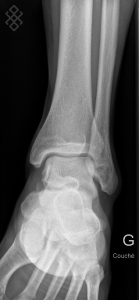

Radiographie de la Cheville